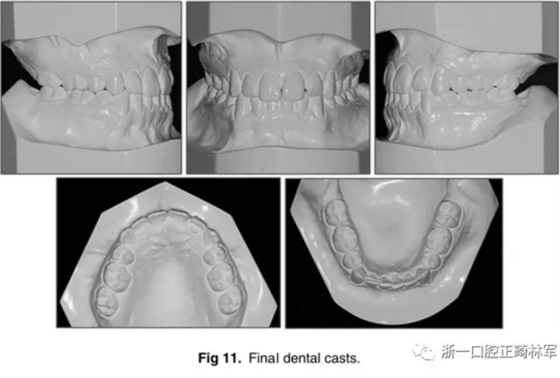

口內(nèi)相及模型:雙側(cè)磨牙、尖牙I類(lèi)關(guān)系,良好的牙尖交錯(cuò)關(guān)系,覆合、覆蓋正常。

影像學(xué):全景片示:牙根平行度可。頭顱側(cè)位片及疊加圖示:顯著的骨性、牙性改變;其中,最大的改變?yōu)樯舷骂M位置關(guān)系,改變了7mm;由此帶來(lái)的改變?yōu)锳NB角從-4°變?yōu)?°,Wits值由-10mm變?yōu)?1.5mm,上頜突度減小(A-NPer,3mm),上下頜不調(diào)改善(Co-A-Co-Gn,41mm),從而使側(cè)貌更為平直;下頜磨牙遠(yuǎn)中移動(dòng),無(wú)伸長(zhǎng)、傾斜,反映了下頜整體的遠(yuǎn)中移動(dòng);上下切牙傾角糾正(1:NA,7mm、25°; 1:NB,4.5mm、20°; IMPA,78°),從而改善了在基骨中的位置。

功能:前伸合的切牙引導(dǎo)與側(cè)方合的尖牙引導(dǎo)得以實(shí)現(xiàn)。

側(cè)貌:上唇突度增大4mm(至S線0mm),整體側(cè)貌更為和諧。

5年隨訪:治療結(jié)果保持穩(wěn)定,無(wú)明顯復(fù)發(fā),但下頜中線有輕微偏移;下頜磨牙位置始終保持穩(wěn)定。